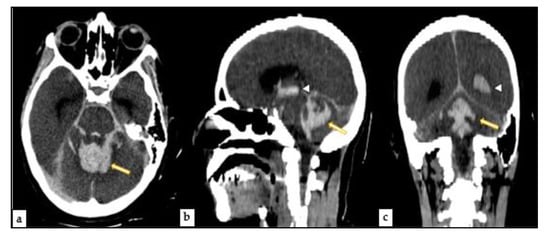

2.3. Post-Mortem Computed Tomography (PMCT)

2.4.2. Central Nervous System Findings